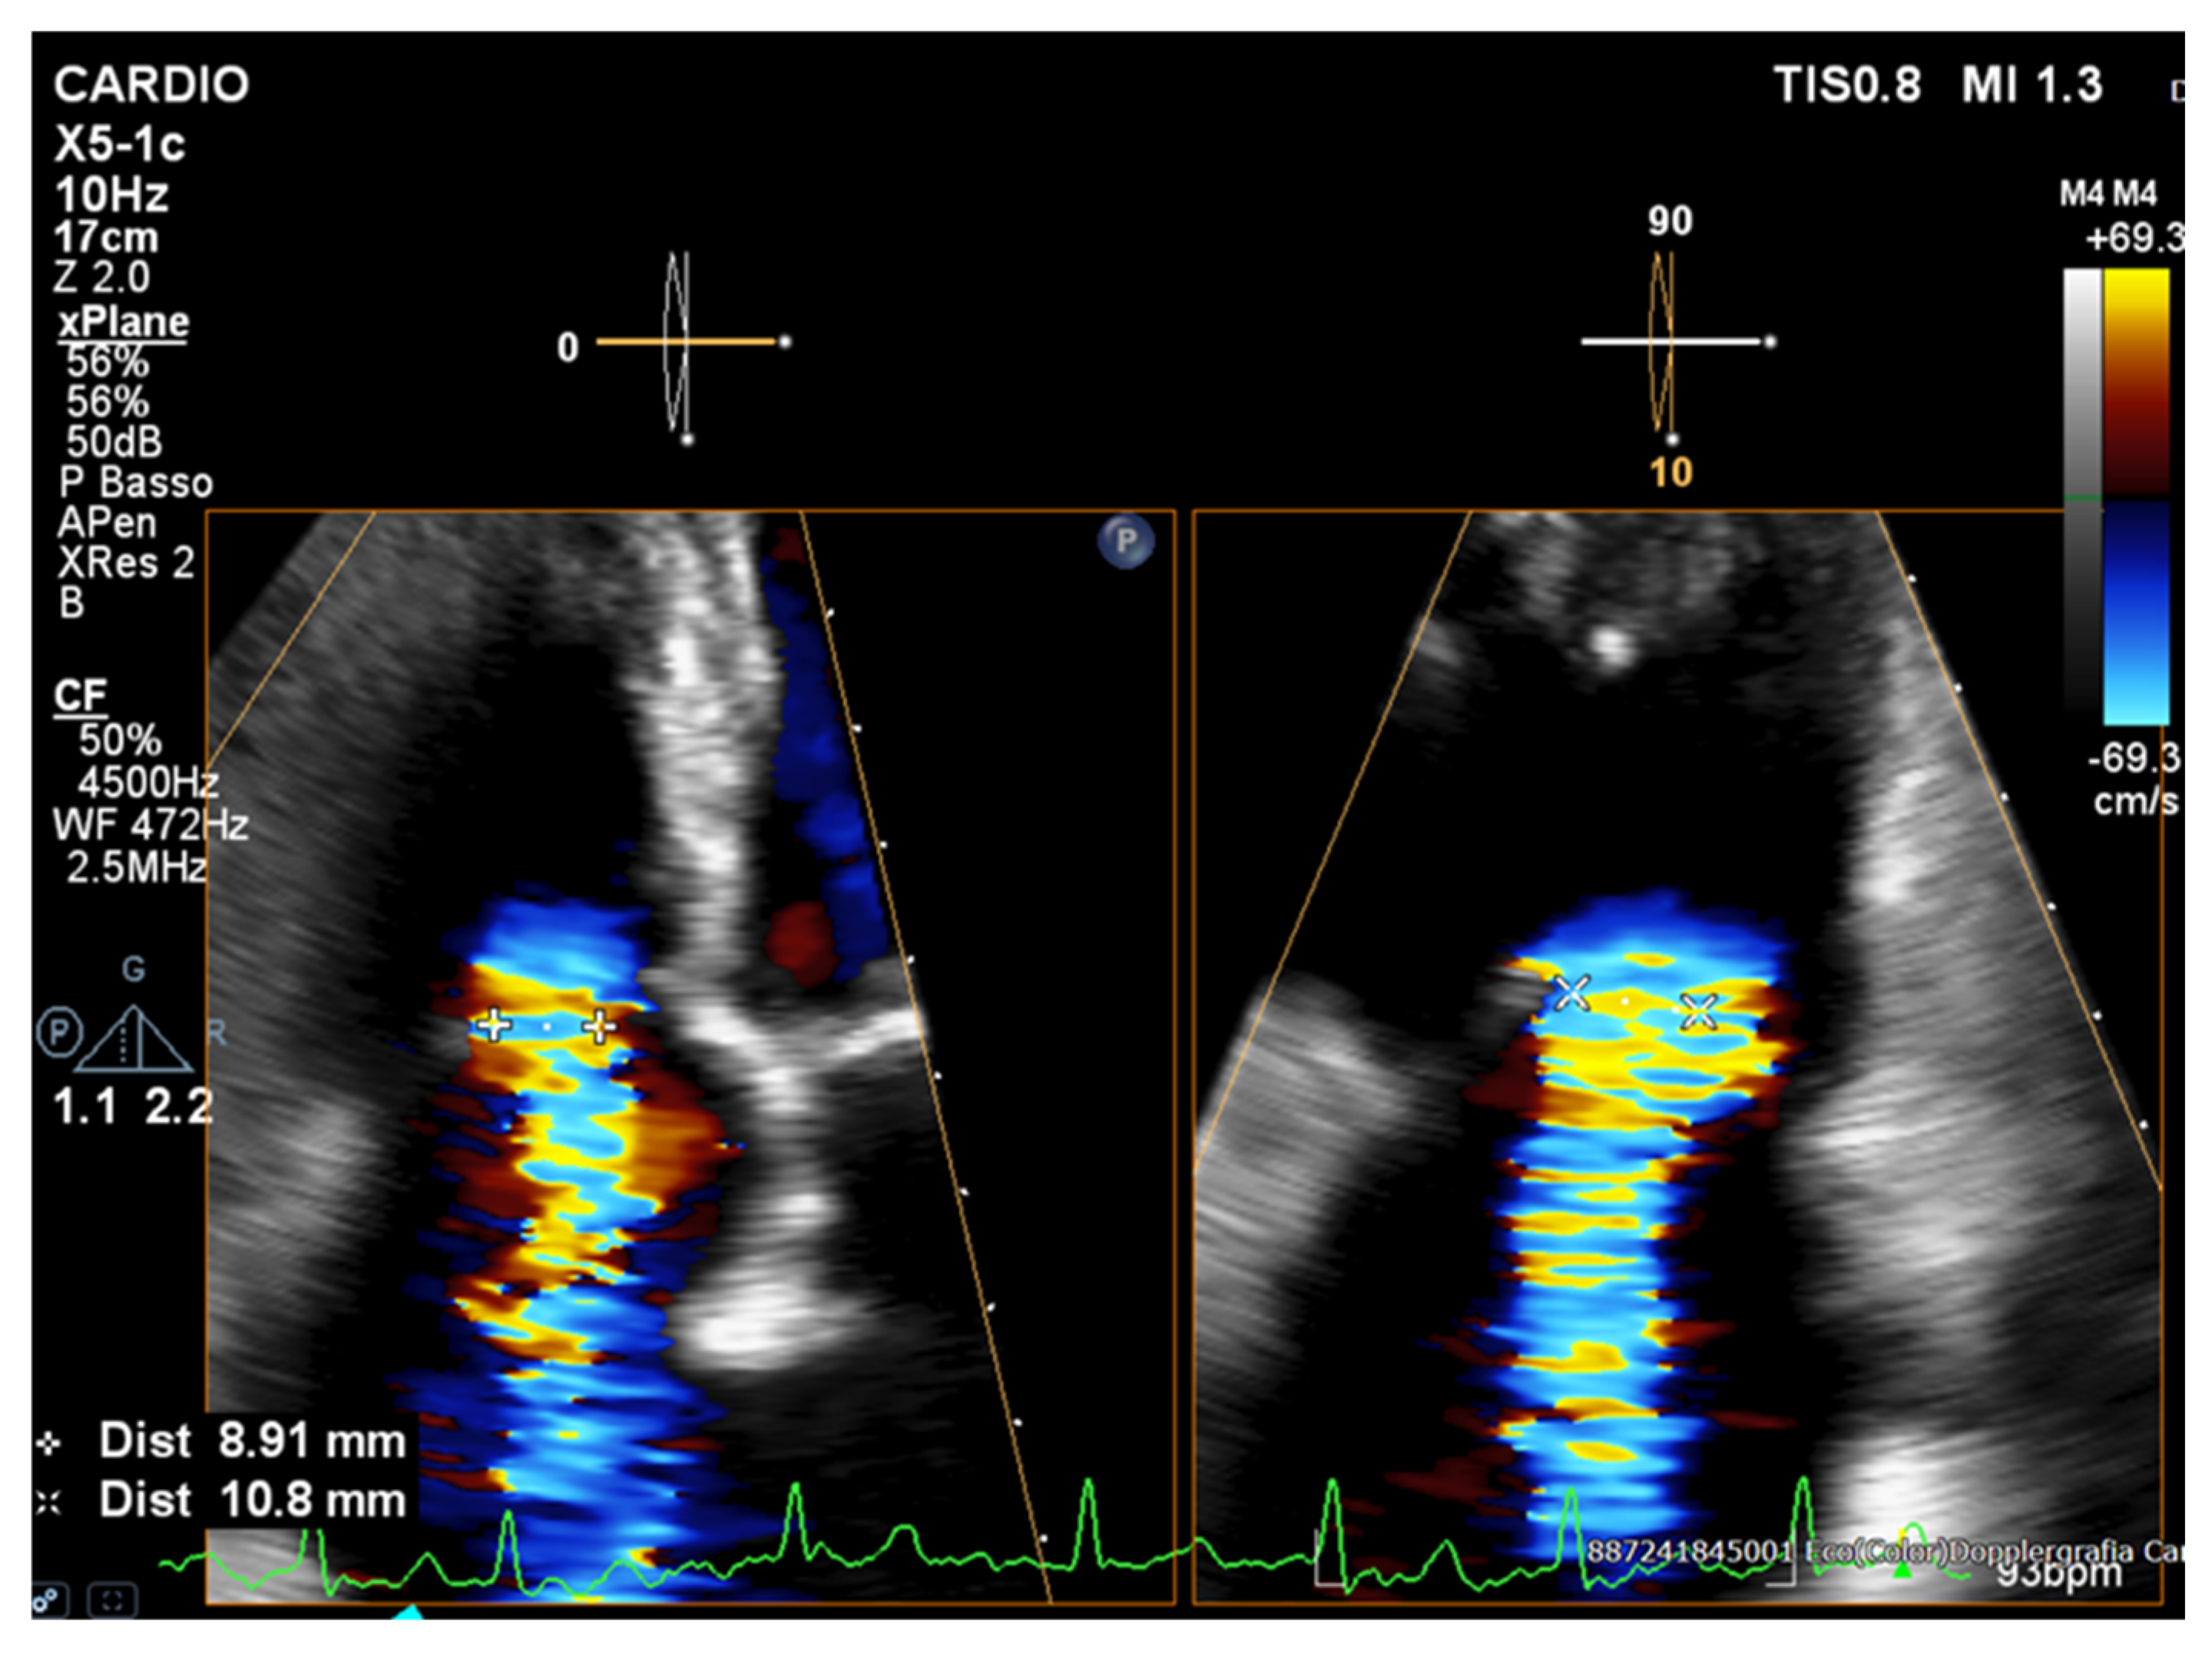

- Chouchani, M.; Michaelsen, J.; Langenbrink, L.; Piatkowski, M.; Altiok, E.; Hoffmann, R. Quantification of Tricuspid Regurgitation Area by 3-dimensional Color Doppler Echocardiography Considering Different Clinical Settings. Echocardiography 2020, 37, 1120–1129. [Google Scholar] [CrossRef]